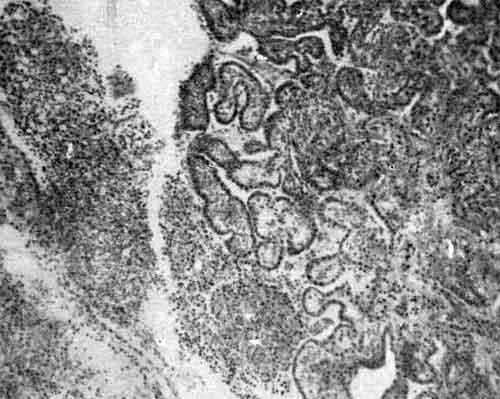

Сосудистое сплетение: набухание и инфильтрация эпителия ворсинок. Воспалительные изменения в сосудистом сплетении. Сосуды гиперемированы. Видны псаммоматозные тельца.

Множественные туберкулы в сосудистом сплетении

Набухание и инфильтрация эпителия ворсинок сосудистого сплетения

В сосудистом сплетении обнаруживаются различные стадии изменения — от умеренных инфильтратов до значительных пролиферативно-продуктивных изменений с наличием типичных бугорков: ворсинки изменены, набухшие и инфильтрированные.